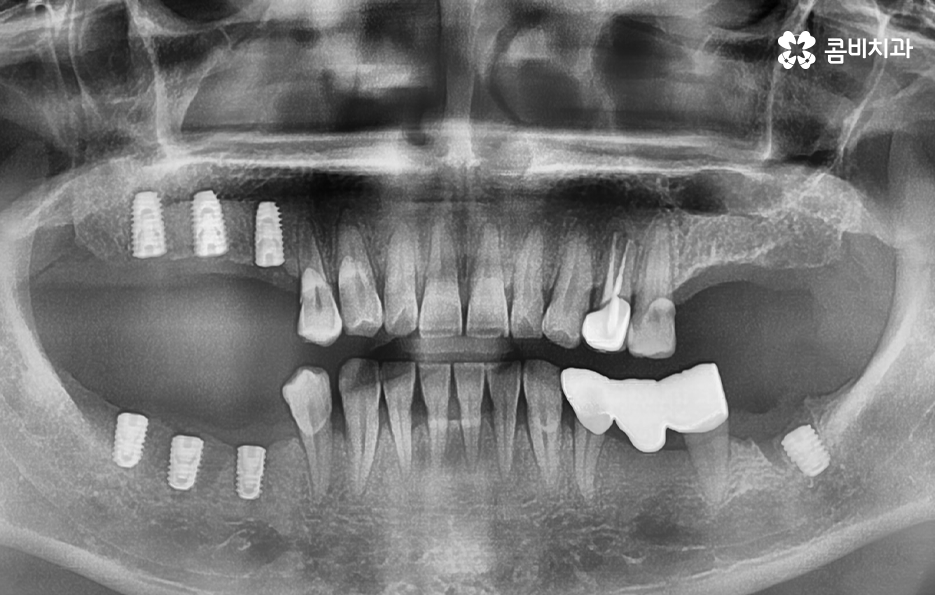

특히 30대 이후에는 충치 외에도 치주염이 점점 심해져서 치아를 발치하게 되는 사례가 많기 때문에 임플란트 치료 과정에서 뼈이식을 함께 고려해야 하는 경우도 있는데요. 오늘은 40대임플란트 이제 알아보시는 분들을 위해 40대 이기 때문에 좀더 고민해야 하는 점들과 치료 과정, 주의사항에 대해 알아볼 거예요

40대임플란트 치료에 대해 알아보신다면 우선 치아를 상실한 원인에 따라서 치료 방법이 다소 차이가 날 수 있는데요. 대표적으로 충치가 심해져서 발치를 하게 된 사례와 치주염으로 인해 잇몸이 약해져서 발치하게 된 사례로 구분해 본다면 충치 만으로 치아를 발치한 경우 잇몸 상태가 양호할 때 원데이임플란트로도 치료가 진행되거나 무난하게는 일반적인 임플란트 치료 과정으로 진행될 수 있어요

반면에 치주염이 심해져서 치조골이 녹아내리고 이미 치아의 뿌리가 보일 정도로 잇몸이 약해진 상태에는 치아 발치 후 잇몸이 충분히 회복한 뒤 임플란트를 식립할 수 있는 잇몸 뼈가 충분한지 확인 후 경우에 따라서는 뼈이식이 추가될 수 있는데요.

임플란트는 잇몸 뼈에 식립하기 때문에 치주염으로 인해 잇몸 뼈가 부족하거나 치아를 발치 후 오랜 시간이 지난 다음에 임플란트를 하게 될 경우 임플란트를 식립할 충분한 잇몸 뼈의 확보를 위해 뼈이식을 받아야 할 수 있어요

생각보다 많은 40대 환자분들이 충치 외에도 치주염으로 인해 풍치 진단을 받고 치아를 발치하게 되는 사례가 많기 때문에 40대임플란트 치료 과정 중에 잇몸 뼈의 중요성에 대해 설명드려야만 왜 나는 치료 방법이 달라지고 뼈이식을 받아야 하는지 등과 같은 궁금증을 해소할 수 있을 거예요

하지만 앞서 설명드린 것처럼 30대 이후에는 치주질환을 앓게 되는 분들이 급격히 늘어나며 치주질환 관리가 잘 안되신 분들의 경우 40대에도 치주염으로 인해 치아를 상당수 잃게 되는 사례도 적지 않게 확인되고 있어요